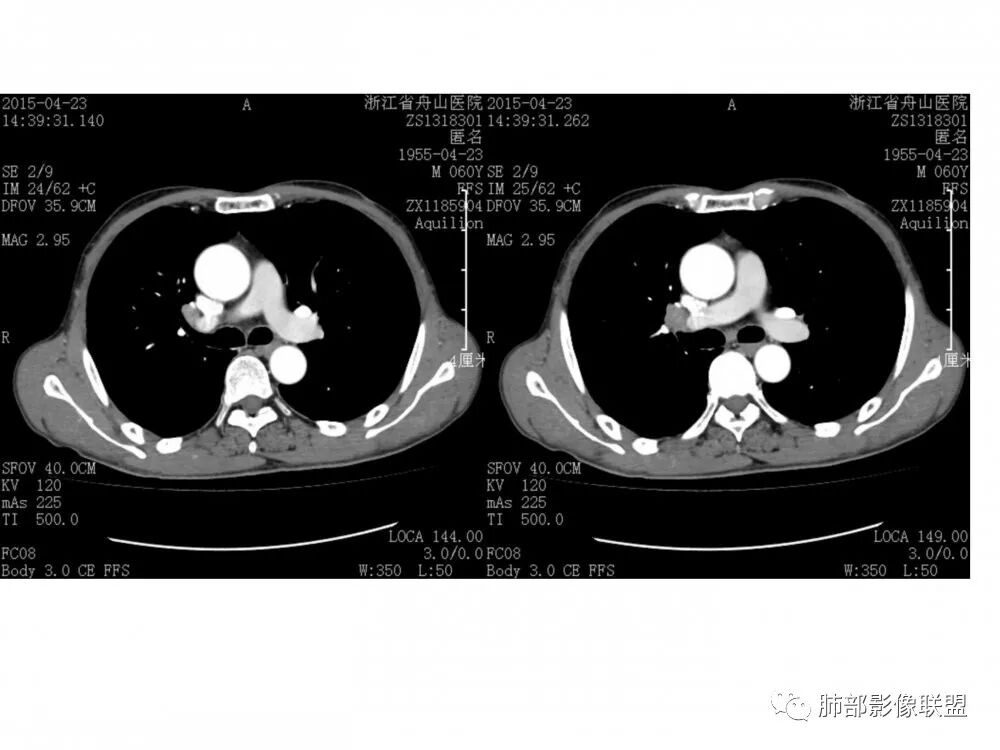

右肺下叶支气管开口新生物,轴位管腔及纵向基底干大部分受累狭窄,支气管管壁破坏明显,强化较低不均匀,肺门、7组、4R淋巴结肿大,考虑恶性支气管腔内肿瘤,鳞癌可能性大,需要与类癌、涎腺类肿瘤鉴别

老年男性,60岁,右下肺门肿块,右下支气管粘膜下生长,并堵塞,无明显阻塞性肺炎和肺不张,早期多发淋巴结转移,似不均匀强化。综合看恶性程度高,考虑大细胞癌,一个不支持点,大细胞癌外周多见。

优先需要与小细胞癌鉴别,再鳞癌鉴别。肿瘤恶性程度排序,小大腺鳞类。小细胞癌不支持点是:1.沿着支气管粘膜下生长,支气管阻塞轻,爬行征;2.包绕血管,冰冻纵隔,有可能病灶比较小,所以没那么快包裹;这例这点不符合。其他倒是符合中央型小细胞癌,比如转移早,恶性程度高。

男,60岁,右肺下叶支气管开口新生物,轴位管腔及纵向基底干大部分受累狭窄,支气管管壁破坏并突破形成腔外肿块,强化较低不均匀,右肺门、7组、4R淋巴结肿大,考虑恶性没问题,鳞癌可能性大,类癌、粘液表皮样癌,乳头状瘤待排。

右肺下叶支气管不规则软组织肿块,病灶沿支气管生长,有一定的张力,部分包绕支气管壁,增强病灶内可见中度强化,内部有延迟强化的特点,周围淋巴结增大,诊断恶性病变无疑,远端无明显支气管阻塞,主要考虑粘液表皮癌,腺样囊腺癌,鳞癌之间鉴别,病灶有类似神经源性病变生长方式,腺样囊腺癌,其次考虑鳞癌或粘液表皮癌。